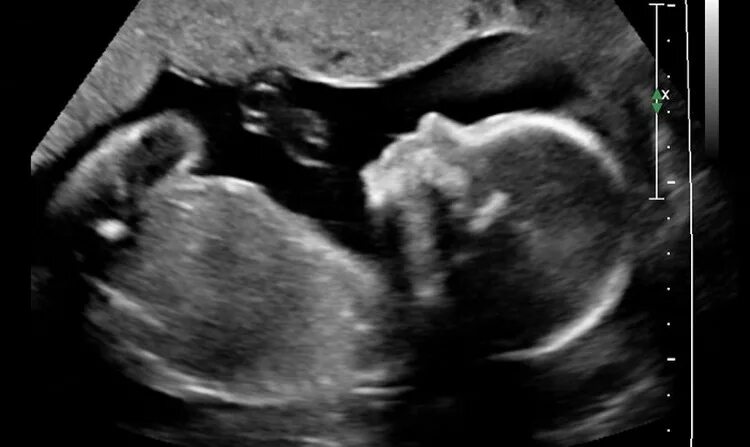

Ребенок в животе 22 недели